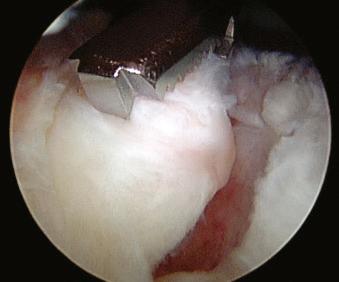

The arthroscope is rotated so that it points directly down at the rotator cuff tear. With small to medium-sized tears, their size and geometry are easily appreciated. Tear size is measured by comparing it to the known diameter of the lateral cannula or measuring it with an arthroscopic probe. The length of the tear from anterior to posterior, as well as the amount of medial retraction, is noted ( Figs. 12.26–12.31 ).

FIGURE 12.26, Introduce the measuring probe.

FIGURE 12.27, Measure the rotator cuff tear.

FIGURE 12.28, Transverse tear.

FIGURE 12.29, Transverse tear.

FIGURE 12.30, Elliptical tear.

FIGURE 12.31, Elliptical tear.